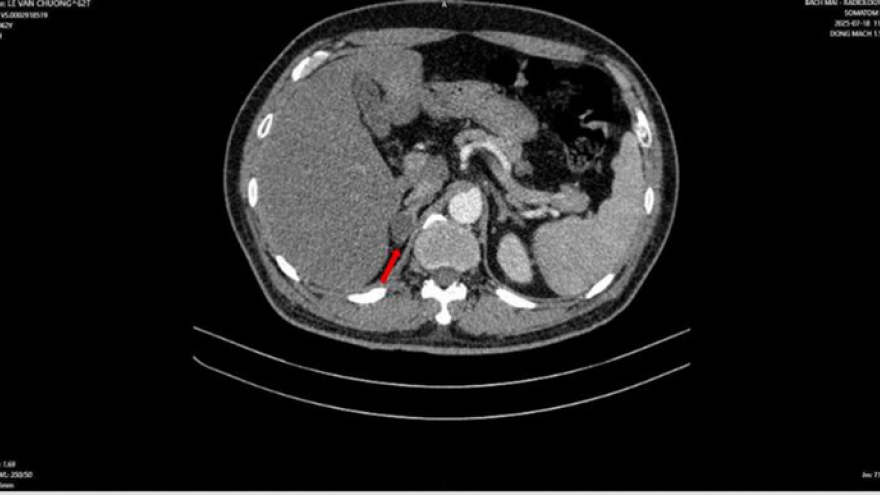

VOV.VN - Người đàn ông 63 tuổi mắc đồng thời hai loại ung thư nguyên phát gồm ung thư phổi và ung thư tuyến tiền liệt.